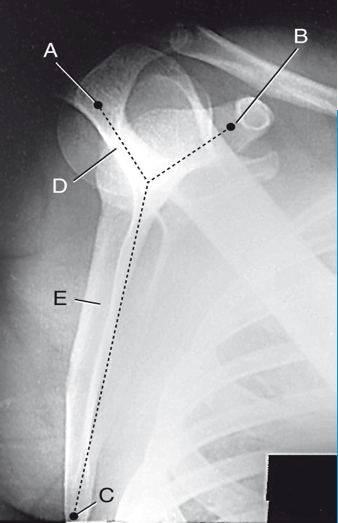

A

coracoid process

B

inferior angle

C

scapular spine

D

body of scapula

E